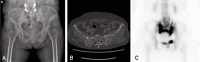

Materials and methods: Fifteen patients diagnosed with pelvic insufficiency fractures were evaluated retrospectively. All patients had osteoporosis with mean lumbar T score of -3.9 (range, -3.1 to -6.4) and the mean age was 76.5 years. In all cases, simple radiography and computed tomography was used for final diagnosis; additional magnetic resonance imaging and technetium bone scans were used to confirm the diagnosis in 2 and 6 patients, respectively. Initial conservative treatment was used in all cases; treatment with PTH was applied in 5 cases. Radiological follow-up was done every 4 weeks up to 6 months and every 3 months thereafter. Symptom improvement was measured using visual analogue scale (VAS) score.

Results: Fractures were located: i) sacrum and pubis (9 cases), ii) isolated sacrum (4 cases) and iii) isolated pubis (2 cases). One case showed fracture displacement and pain aggravation at 4 week follow-up which was treated with percutaneous sacro-iliac fixation using cannulated screws. Duration of bone union was significantly shorter in the patients who used PTH (P<0.05). VAS scores were also lower in the group treated with PTH; however, statistical significance was not reached.